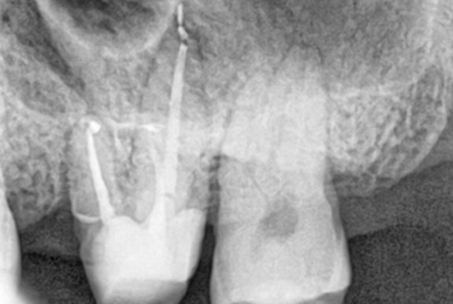

The images above show actual cases treated at SMILE FACE DENTAL CLINIC.

To a non-specialist, they may appear to be ordinary X-rays, but dentists can instantly recognize them.

They can appreciate both the complexity of the treatment and the care and precision involved.